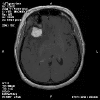

Radiology of the case:

T1-weighed MR images demonstrate an extraaxial, dural based mass involving the right supraorbital region  (Panel A and B). The mass shows homogeneous enhancement  (Panel C). CT scan demonstrates as well as rim calcification (Panel E). On T2-weighed imagers, significant vasogenic edema is demonstrated despite the small size of the lesion and the extraaxial location (Panel D).